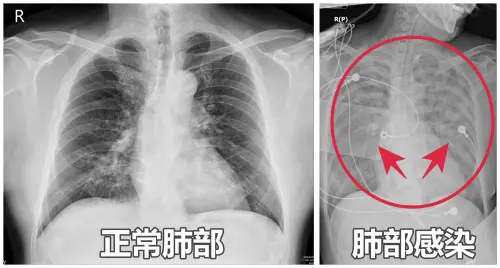

65歲女嗜睡、胃口差!如「靈魂出竅」 醫一照:雙肺全白

一位65歲女性日前因嗜睡、咳嗽、全身無力及胃口不佳掛急診,家人反映患者像「靈魂出竅」,測量血氧後只剩下90%,X光更發現「雙肺白掉一大片」,評估是肺炎惹禍,...

嗜睡咳嗽沒食慾!醫示警肺炎「變大白肺」恐敗血症:高風險族群曝

亞洲大學附屬醫院醫師謝逸安表示,65歲李姓闆娘最近嚴重嗜睡、咳嗽、胃口差,被家人形容「像靈魂出竅」,日前因全身無力送急診,檢查發現血氧僅剩90%,且X光竟顯...

咳嗽、嗜睡別輕忽 婦急診驚見雙肺白成一片

65歲李姓闆娘平日精神硬朗、經營五金行和顧客談笑風生,沒想到日前卻因為嗜睡、咳嗽、全身無力和食慾不振,讓家人驚呼「像靈魂出竅」。送醫急診後,護理師發現她...

肺部影像若出現大片白影,常被懷疑是肺炎,40歲魏先生卻確診為罕見的「肺部蛋白質沉積症」,靠「全肺灌洗術」才恢復順暢呼吸;醫師表示,這種疾病會導致蛋白質堵...